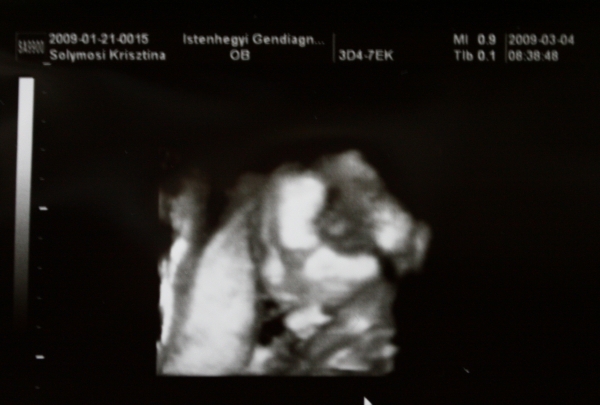

Kukorék Till jelentkezik!!!